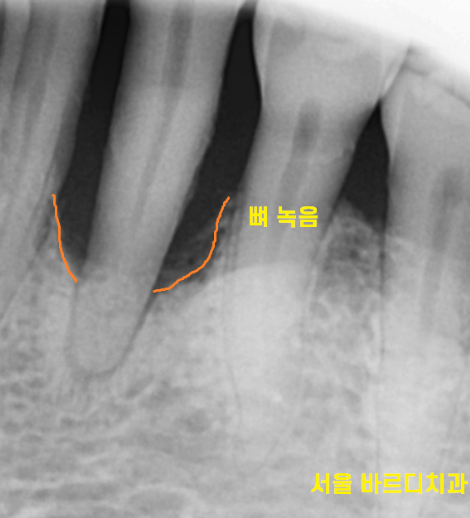

x-ray 상에서도 잇몸이 많이 녹아있네요ㅠㅠ

잇몸뼈가 많이 녹아

치아 뿌리만 겨우 붙잡고 있습니다.

붙잡고 있는게 얼마 없어

식사할때마다 흔들렸을꺼고

많이 불편하셨겠어요~